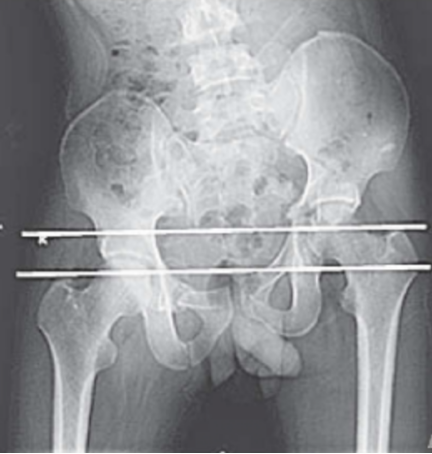

(2)陈旧性骶髂关节骨折脱位的治疗:此类损伤处理困难。因为骨痂多、粘连重、手术时出血多、复位困难。手术治疗是针对明显的遗留症状,如负重时的放射性神经痛、行走痛、步态明显异常、下肢不等长。对于神经症状,一般采用神经营养药物等非手术治疗,当有影像学证据表明神经受到卡压时,可以实行前路神经探查松解术。如果骶髂关节陈旧脱位、骨盆倾斜导致下肢不等长,可以根据具体情况采取肢体短缩术、肢体延长术、髋骨截骨术,或者畸形愈合处截骨术等方法进行治疗。如下图所示,一位女性患者因车祸致脑外伤及C3型骨盆骨折,4个月后就诊时骨盆骨折已畸形愈合,肢体不等长达6 cm。骨盆前后位X线片显示左侧髂骨明显上移,使双侧大粗隆不在同一水平(图1)。

图1(图源:作者提供)